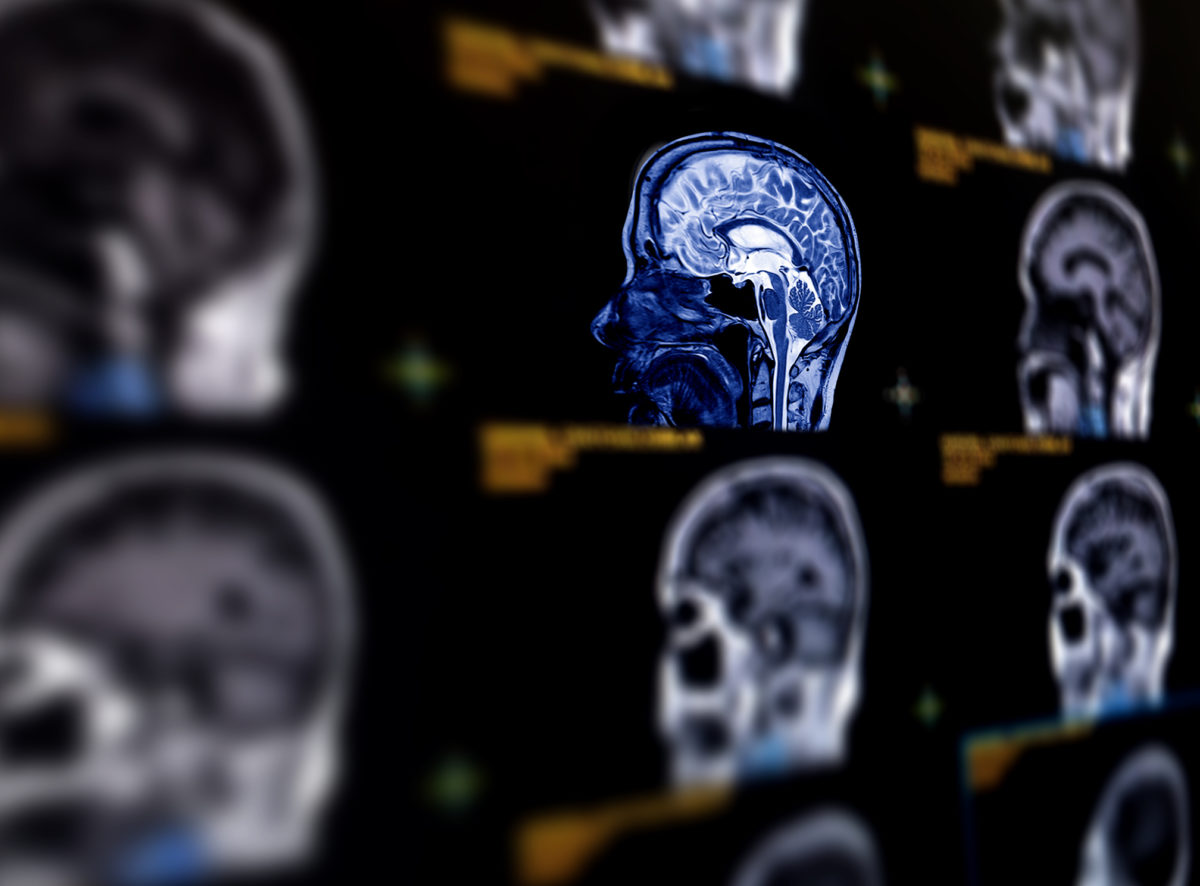

Ισχαιμικό εγκεφαλικό επεισόδιο: 7 παράγοντες θα αυξήσουν δραματικά τους θανάτους τα επόμενα χρόνια

Συγκεκριμένα, σύμφωνα με μελέτη που δημοσιεύτηκε στο ηλεκτρονικό τεύχος του ιατρικού περιοδικού «Neurology» της Αμερικανικής Ακαδημίας Νευρολογίας, οι θάνατοι παγκοσμίως από ισχαιμικό εγκεφαλικό επεισόδιο, τον πιο κοινό τύπο εγκεφαλικού επεισοδίου, ήταν 2,04 εκατομμύρια το 1990 και αυξήθηκαν σε 3,29 εκατομμύρια το 2019. Οι επιστήμονες προβλέπουν ότι η αύξηση θα είναι δραματική ως το 2030.